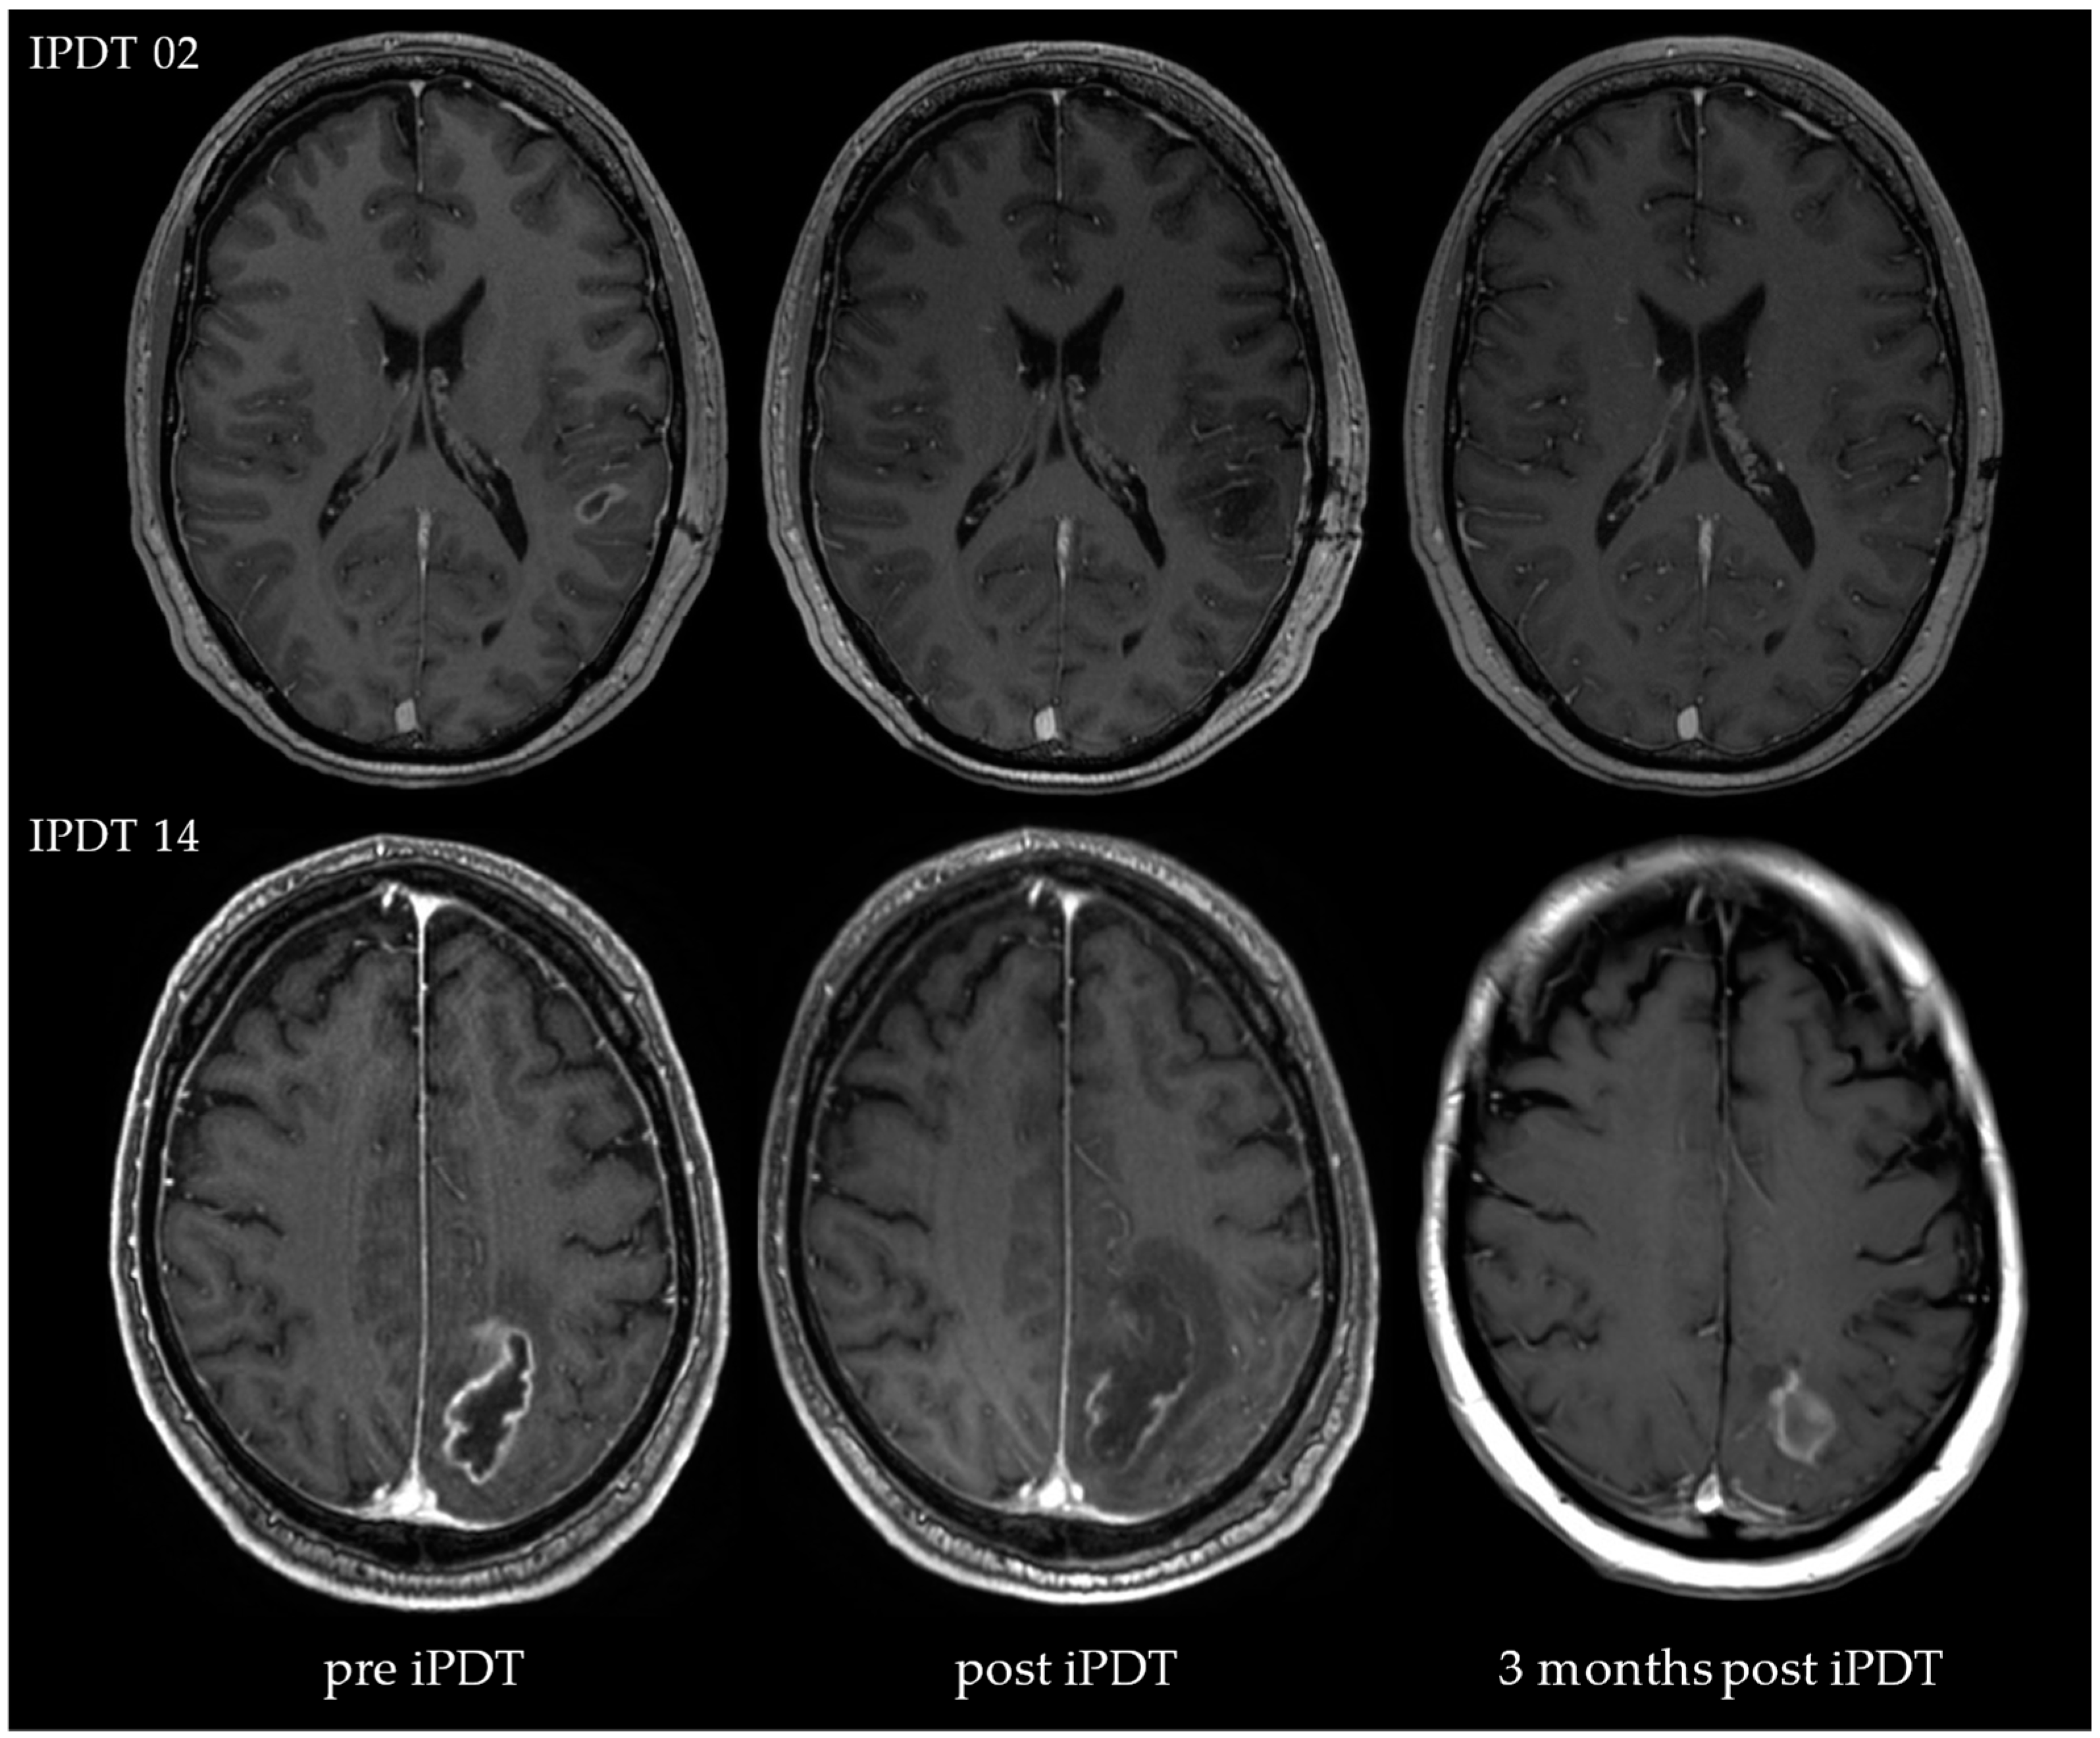

| IPDT 14 (⟳ 36, † 44) | m | 54.3 | 35.7 | 43.9 | 7.8 | † |

| IPDT 14 (⟳ 36, † 44) | yes | no | no | 15% | parieto-occipital | left | partially | 8 |